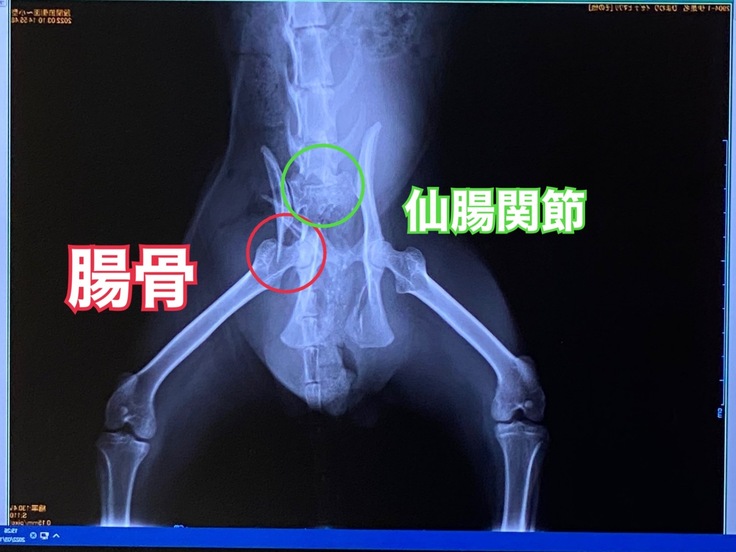

近所の病院で血液検査やレントゲンを撮ってもらい、【骨盤骨折】という診断を受けましたが、骨が守ってくれたおかげで幸いにも内臓に損傷はありませんでした。

受け入れ先の病院を紹介していただいたのでそこでも状態を診てもらい、改めて骨盤(仙腸関節・腸骨)が骨折していることをレントゲンで確認しました。